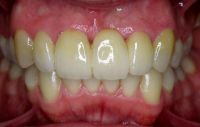

Na de behandeling met composiet

Door het composiet is er weer een dikke, stevige laag ontstaan aan de binnenzijde die niet snel zal afbreken. De tanden zijn hierdoor ook weer verlengd.